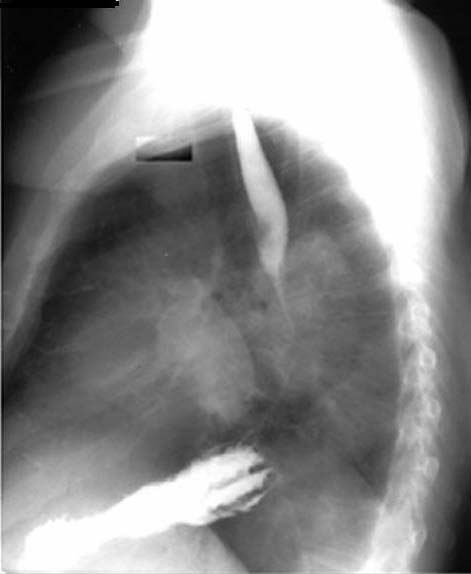

| CXR | Is the Pacemaker inserted from right or left side? | Answer | |